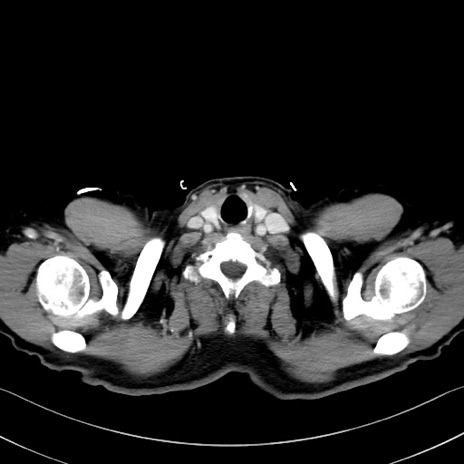

症例35(横断像)

【症例】70歳代 男性

【主訴】腹部膨満、嘔吐

【現病歴】昨日より腹部膨満感出現。本日増悪し、仙痛出現。嘔吐あり、受診。

【既往歴】糖尿病、胆摘後

【身体所見】BP 149/80mmHg、HR 74/min、BT 35.9℃、腹部:膨満、軟、圧痛なし。腸雑音減弱あり。上腹部正中切開瘢痕あり。

【データ】WBC 13500、CRP 1.72